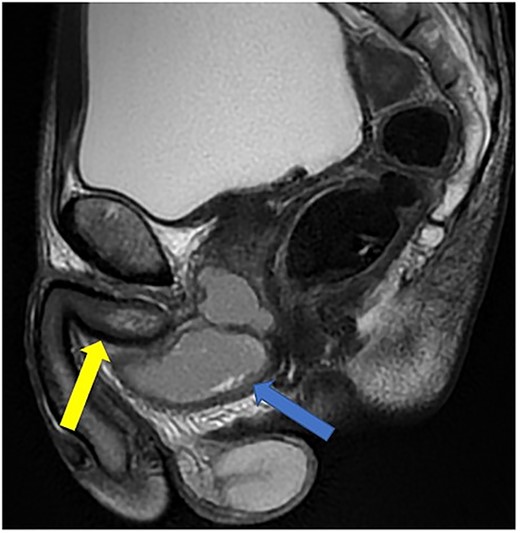

Case 1: sagittal and coronal T2-weighted images showing the collection (blue arrow) inferior to the prostate, and involving the corpus spongiosum (yellow arrow).

Imaging was suggestive of an infected Cowper’s syringocele. As the patient was clinically stable, a trial of antibiotic therapy was suggested. Repeat MRI a week later showed that the collection had extended into the corpus spongiosum, which now appeared expanded with the fluid density signal (Fig. 1). On a review, the urethral catheter was thought to be impairing potential drainage of the collection. It was removed, and a suprapubic catheter was inserted. Ultrasound guided aspiration failed to drain a significant amount of pus, which also grew S. anginosus. There was also radiological suspicion of a colovesical fistula. The patient was reviewed by the colorectal surgeons, who felt that as there were no other symptoms relating to the fistula, and the patient was physiologically frail, and defunctioning of the bowel would be inappropriate. Likewise, the patient was deemed too frail for any surgical management of the collection. He was discharged after a total of 6 weeks’ antibiotics. Repeat MRI 4 months later (Fig. 2) showed a smaller but persistent collection.